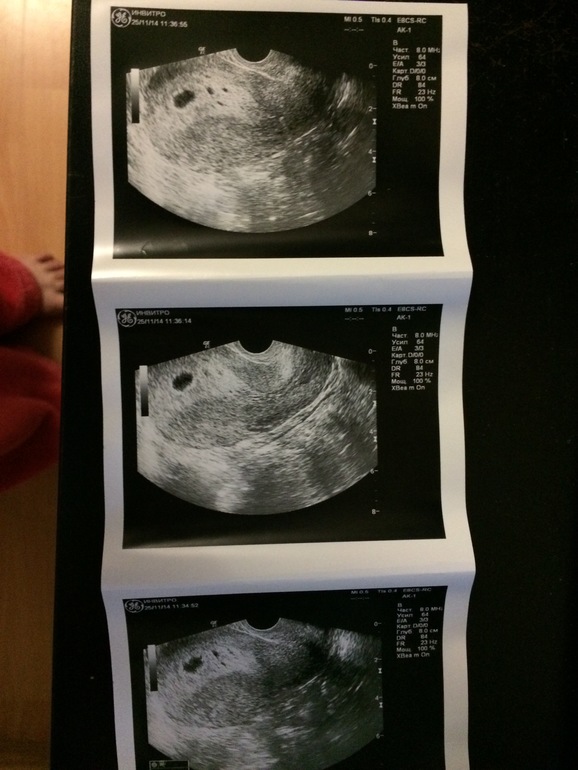

Девочки, ПЯ вижу, а вот рядом пятна, что это? Врач не сказала, а я сразу не спросила. Теперь переживаю, в голову лезет пузырный занос(((( гляньте,пожалуйста!!!